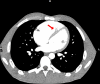

Wellens' syndrome is described as characteristic biphasic or symmetrical T-wave inversion with normal precordial R-wave progression and the absence of Q waves in the right precordial leads. It is seen during chest pain-free interval in a subset of patients with unstable angina. Wellens' syndrome is associated with critical stenosis of proximal left anterior descending (LAD) coronary artery. Similar characteristic ECG changes associated with causes other than LAD stenosis have been described as pseudo-Wellens' syndrome. In this case report, we present a young 22-year-old man who presented with characteristic Wellens' ECG changes in the setting of pulmonary embolism with right ventricular strain. T-wave inversion in right precordial leads is a well-recognised ECG manifestation of right ventricular strain; however, biphasic T waves in the setting of pulmonary embolism are rare. Pulmonary embolism was seen in our patient a week after starting risperidone. There is a reported association between antipsychotic drugs and increased risk of thromboembolism. Risperidone could have potentially contributed to the pulmonary embolism in our patient given the temporal association and absence of risk factors.